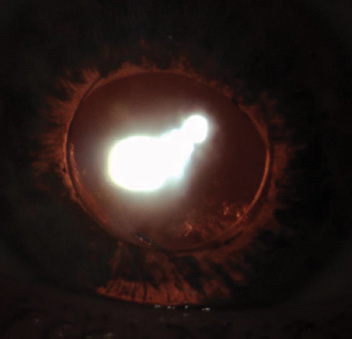

Figure 3. Postoperative slit-lamp examination showed the optic captured through a posterior capsulorhexis and the haptics in the sulcus.

In this eye, the posterior capsule remained intact, allowing me to pursue a somewhat infrequently used option. I performed a posterior capsulorhexis and posterior optic capture, while leaving the haptics in the sulcus (Figure 3). This maneuver created some clearance between the IOL and the iris (Figure 4), thus addressing the uveitis-glaucoma-hyphema syndrome, while simultaneously stabilizing and centering the IOL and resolving the patient’s intermittent diplopia.

Postoperatively, the patient no longer had intermittent monocular diplopia. His BCVA improved slightly to 20/30+2. The IOP measured 16 mm Hg off timolol and remained stable for the next 5 years.

Figure 4. Postoperative UBM showed improved centration and clearance between the IOL and iris.